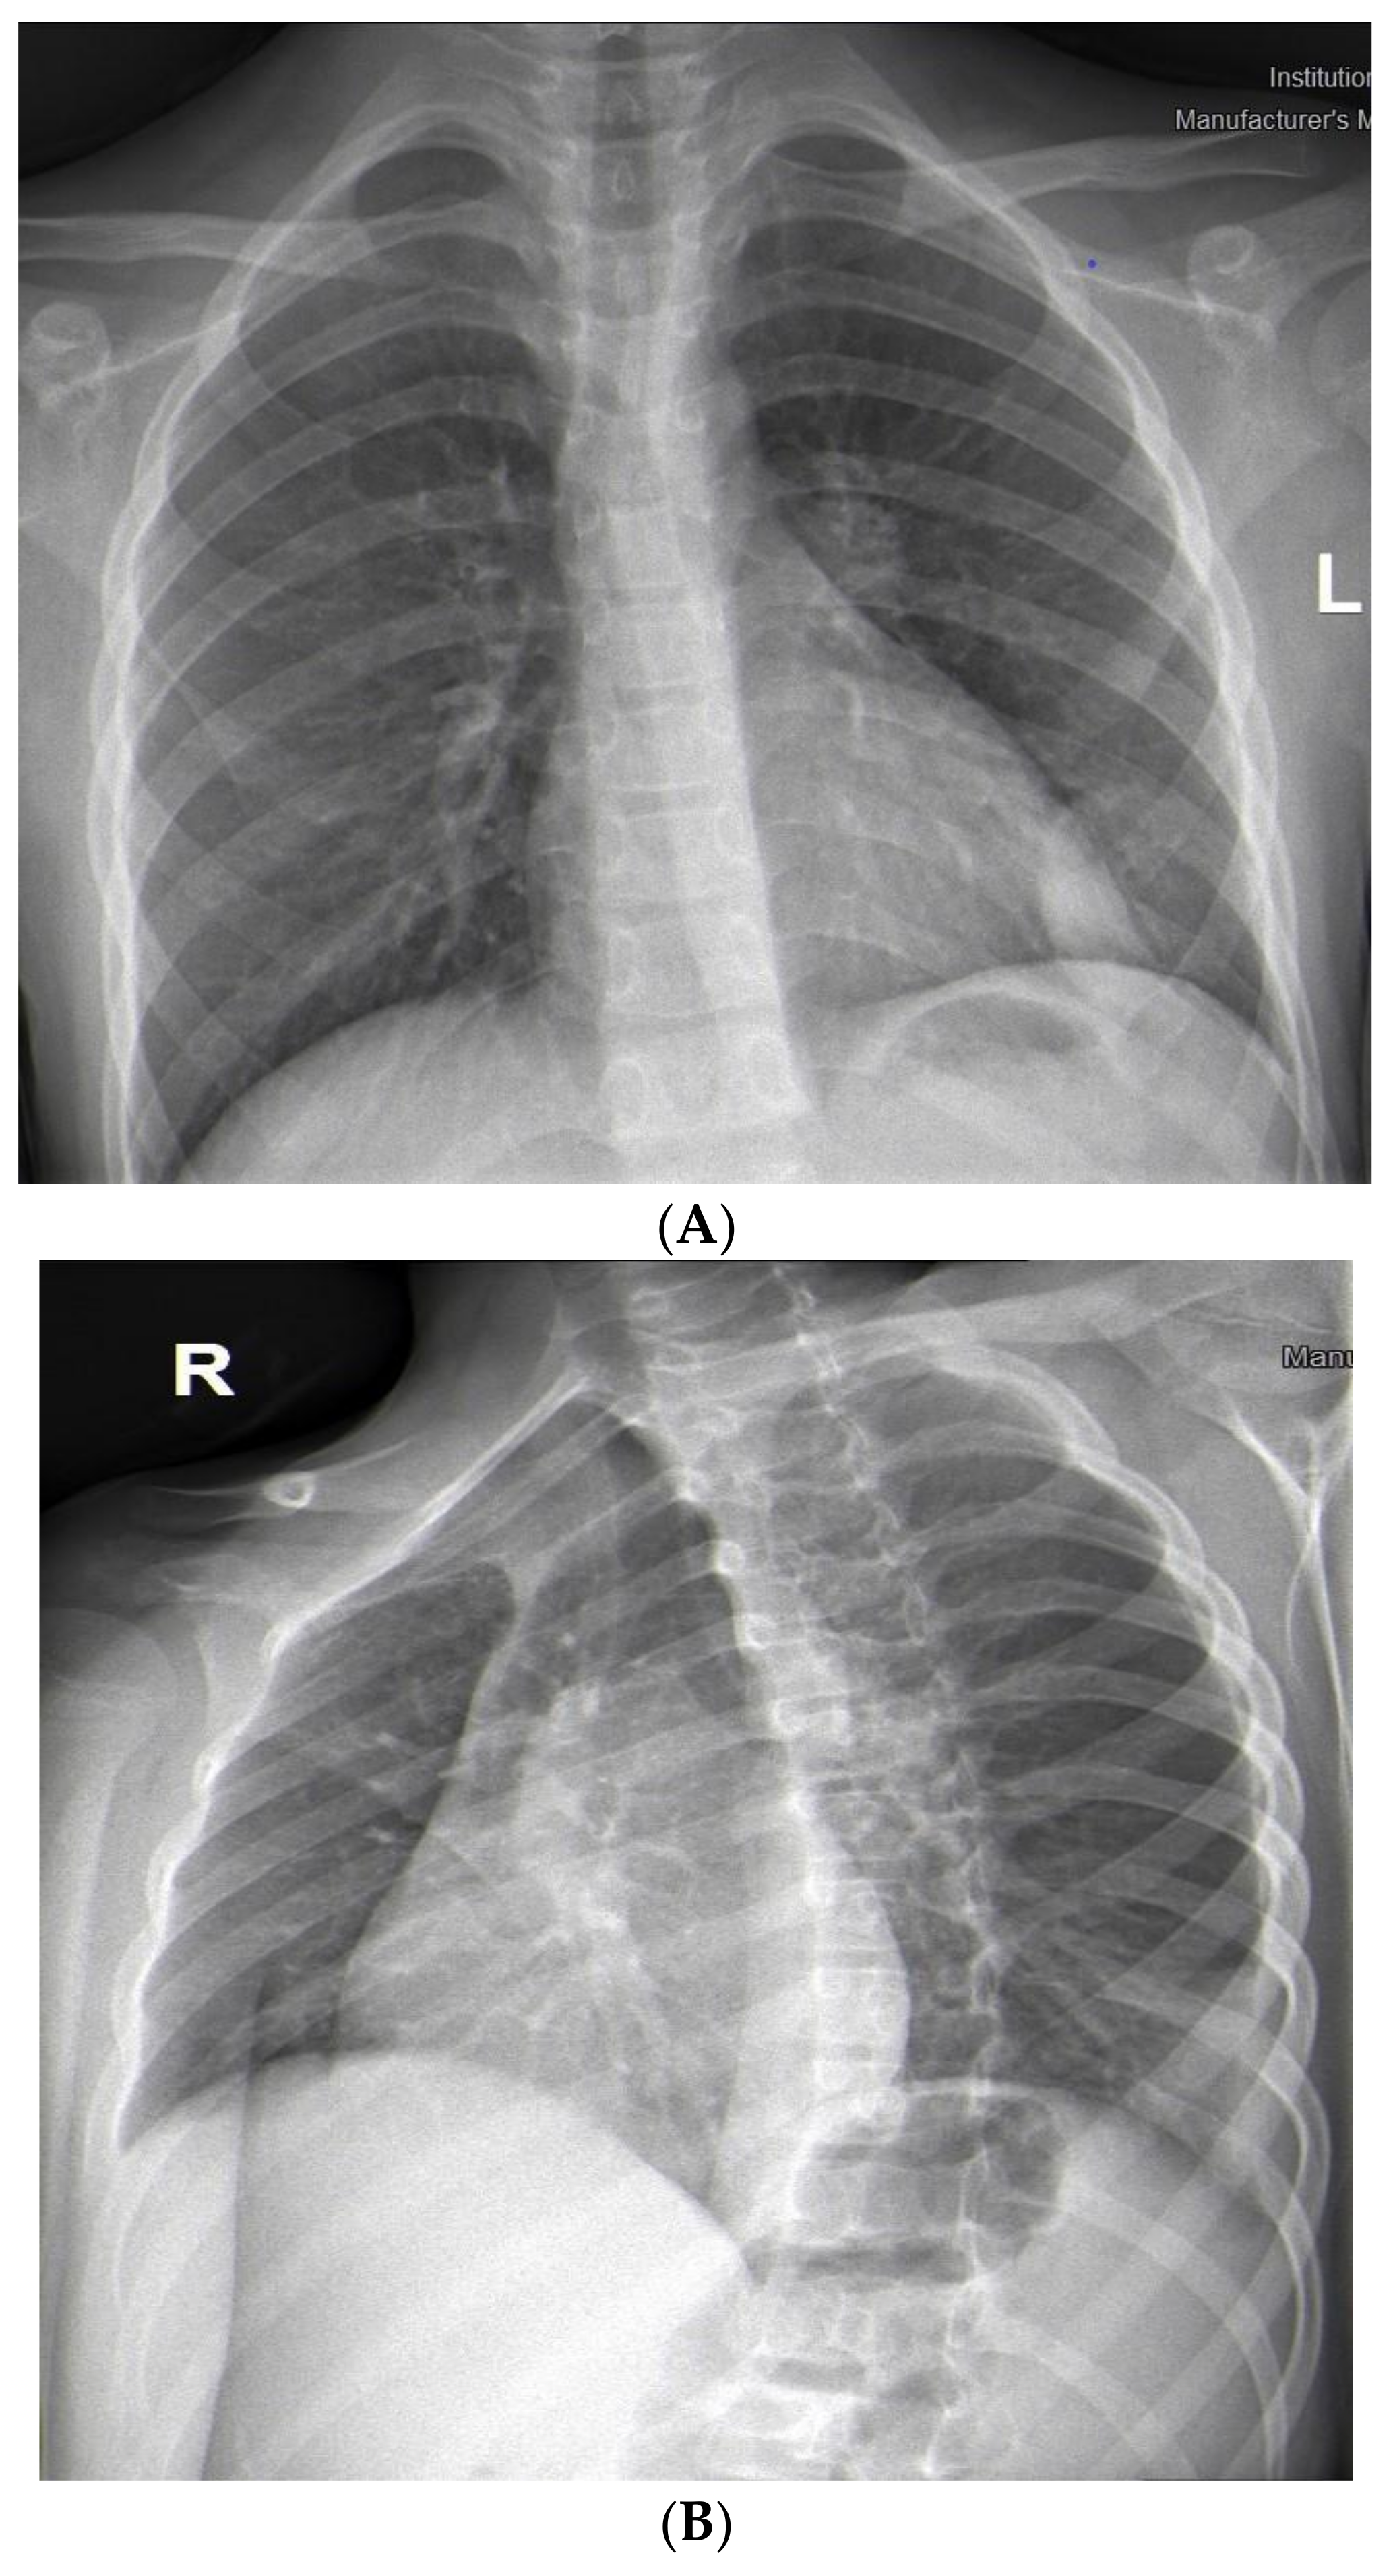

We present a 9-year-old boy with a history of recurrent respiratory infections. In July 2022, the child swallowed an awn during a walk on a field in Northwest Bulgaria, and after two days, he started to cough. On the third day after the accident, he became febrile, and antibiotic therapy was prescribed (Clarithromycin). This treatment was not effective, and the child suffered left-sided chest pain, irradiating to his left shoulder. Nonsteroidal anti-inflammatory drugs were prescribed. On the 10th day, the patient was admitted to the Department of Pediatric Pulmonology for further diagnostic workup and treatment. The child’s condition was stable, with a productive cough and reduced vesicular breathing paravertebrally and axillary on the left side of the chest. His hemodynamic was stable, and his abdomen was not tender, without hepatosplenomegaly. His blood tests showed inflammation—increased C-reactive protein (CRP) 36.29 mg/L and leukocytes 10,9 x109 L, and stable hematological parameters (hemoglobin 126 g/L, hematocrit 39%, erythrocytes count range 4.69, platelets 347). Biochemical markers were also in the normal range—sugar level 6.08 mmol/L, creatinine 42 µmol/L, urea 2 mmol/L, ASAT 15 U/L, ALAT 12 U/L, alkaline phosphatase 127 U/L, total protein 65.3 g/L, albumin 41.26 g/L. Frontal and lateral chest X-rays showed faint reticular and patchy opacities with unclear margins in the lower lobe of the left lung (Figure 1A,B). Treatment comprised antibiotics (Ceftriaxone), corticosteroids (Methylprednisolone), and saline inhalations.

Figure 1. (A). Frontal chest X-ray—faint reticular and patchy opacities with unclear margins were visualized in the lower lobe of the left lung. (B). Lateral chest X-ray.